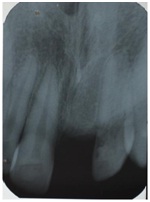

A 12-year-old boy accompanied by his parents reported to the Department of Pedodontics and Preventive Dentistry, with the chief complaint of tooth loss in the upper front region one and half years ago in a road accident. History revealed that the patient had a bicycle accident one and half years earlier and one of the anterior tooth was avulsed and patient brought an avulsed tooth along with him, to replace the saddle. Clinical examination revealed space loss in relation to the maxillary right central incisor, class I molar relation on both sides and maxillary arch oval in shape [Table/Fig-1]. Clinically a 4 mm space loss in relation to 11 was confirmed with intraoral periapical radiograph (IOPA) [Table/Fig-2]. The case was undertaken for space regaining with modified 2 by 3 fixed appliances, then followed by fixed functional space maintainer.

Intra oral periapical radiograph

An 11-year-old boy accompanied by his parents reported to the Department of Pedodontics and Preventive Dentistry, with the chief complaint of tooth lost in the upper front region in a road accident. The parents reported the history of avulsion of left central incisor two years back. Intraoral examination revealed a mixed dentition, maxillary arch was oval in shape and maxillary right and left second premolars were buccally erupting. Mesio-buccal rotations were seen in maxillary second premolars and left maxillary canine. Class I molar relation on both sides and a 3 mm space loss in relation to 21. It was confirmed with IOPA [Table/Fig-8]. The case was undertaken for space regaining with modified 2 by 3 fixed appliances, followed by fixed functional space maintainer.

Intra oral photographs and IOPA